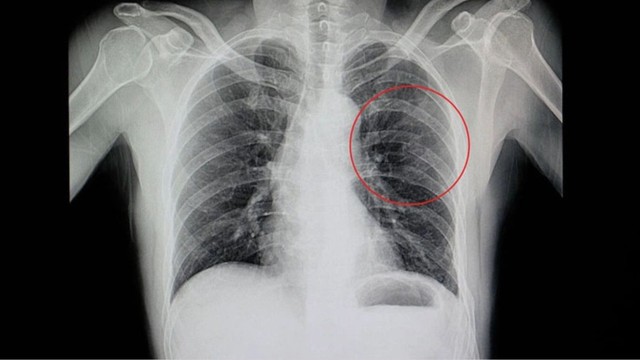

Rạn xương